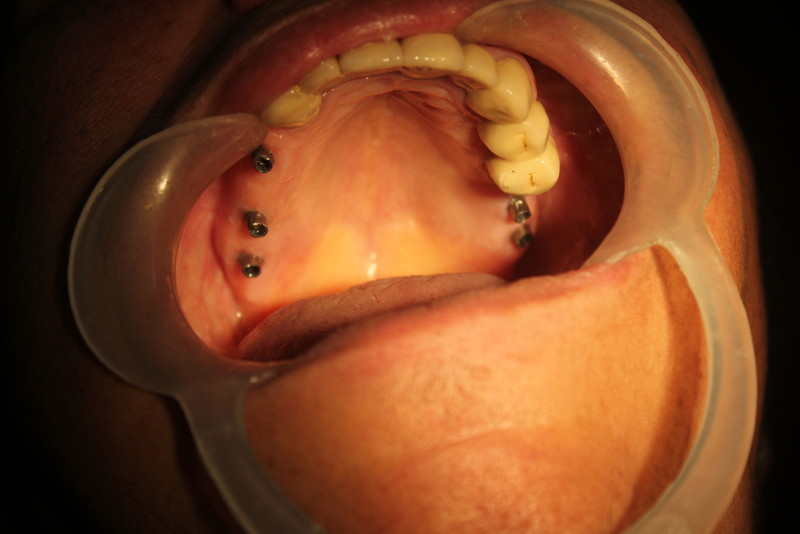

Dental Implants and Autogenous Bone Grafting